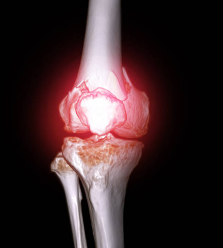

2. 내측 반월상 연골 손상

내측 반월상 연골은 무릎 관절의 쿠션 역할을 하며, 충격을 흡수하고 관절의 움직임을 돕습니다. 내측 반월상 연골이 찢어지거나 파열되면 무릎 안쪽 통증이 발생하며, 부기, 무릎의 잠김 현상, 관절의 움직임 제한 등의 증상이 동반될 수 있습니다. 내측 반월상 연골 손상은 스포츠 활동 중에 갑자기 방향을 바꾸거나 점프하는 경우에 자주 발생합니다.

6. 퇴행성 반월상 연골 파열

퇴행성 반월상 연골 파열은 나이가 들면서 반월상 연골이 약해지고 손상되는 질환입니다. 퇴행성 반월상 연골 파열이 발생하면 무릎 안쪽 통증이 발생하며, 부기, 무릎의 잠김 현상, 관절의 움직임 제한 등의 증상이 동반될 수 있습니다. 퇴행성 반

월상 연골 파열은 특별한 외부 요인 없이도 발생할 수 있으며, 나이가 들수록 더 많이 발생합니다.